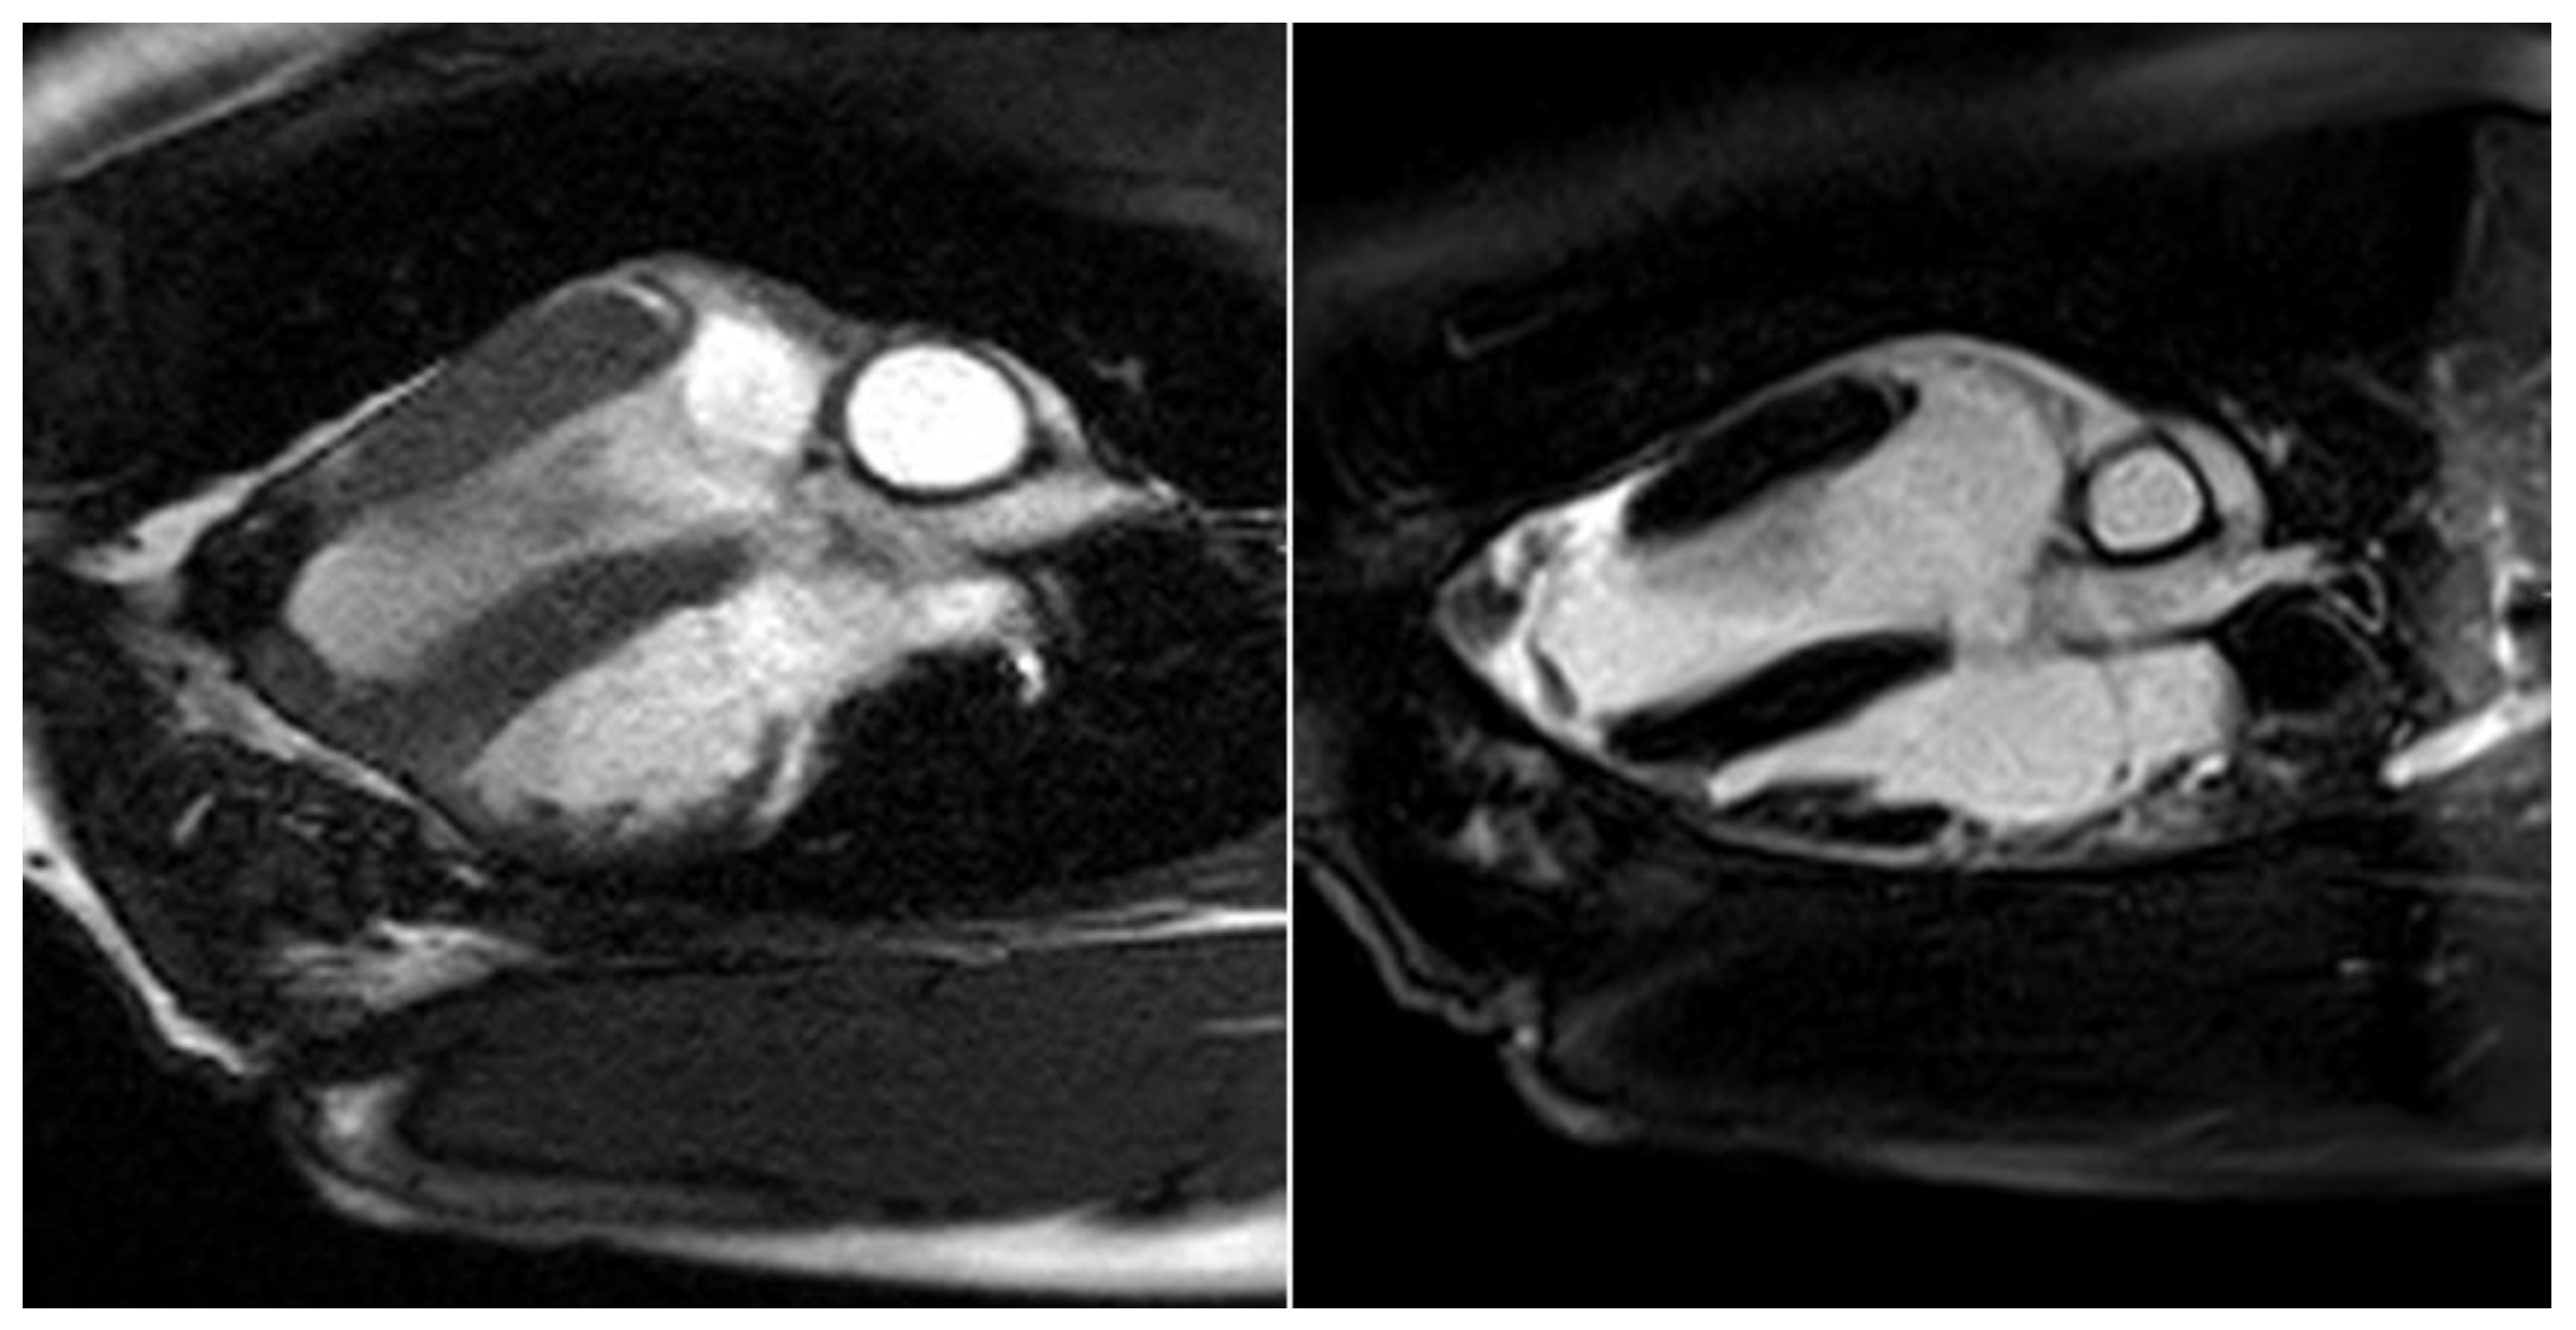

All test animals were examined six months after successful surgery using cardiac MRI to evaluate the morphology and function of the left ventricle, particularly in the area of the transplanted patches of stomach tissue. In line with the macroscopic findings, stable integration of the stomach patch through adjacent cicatricial tissue could be detected in animals without an aneurysm (see Figure 7).

Figure 7.

Cardio MRI six months following myocardial reconstruction with a vascularized stomach patch, stabilized with degradable magnesium alloy scaffolds. Cine SSFP in left ventricular two-chamber view. Left: end-diastolic phase, right: end-systolic phase. Good integration of the transplanted stomach patch.

The border zone between the myocardium and the stomach patch showed an intense late enhancement of the contrast agent as an expression of the adjacent stabilizing fibrotic remodeling processes in these animals (see Figure 8).

Figure 8.

Cardio MRI six months following myocardial reconstruction with a vascularized stomach patch, stabilized with degradable magnesium alloy scaffolds. Delayed enhancement imaging. Left: cine SSFP. Right: four-chamber view with signs of distinct late enhancement in the left ventricular, apical zone, indicating cicatricial remodeling.

However, the left ventricular ejection fraction was still reduced (50%), and the region of the stomach patch was akinetic. There was a paradoxical systolic outward movement of the affected area and a reduction of left ventricular ejection fraction of 15%–18% in the animals with an aneurysm. The aneurysms had a total volume of 12–18 mL. The delayed enhancement of the contrast agent was seen in these animals, mainly in the border zone between the native myocardium and the stomach tissue.